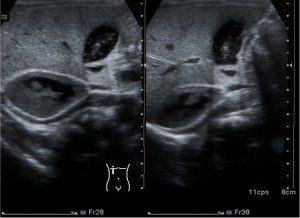

- Colelitiasis: La colelitiasis se refiere a la formación de cálculos biliares en la vesícula biliar. Estos cálculos se pueden identificar en la ecografía como estructuras hiperecogénicas dentro de la vesícula. Pueden variar en tamaño y cantidad. Las colelitiasis deben ser estructuras móviles con sombra acústica posterior e hiperecogénicas.